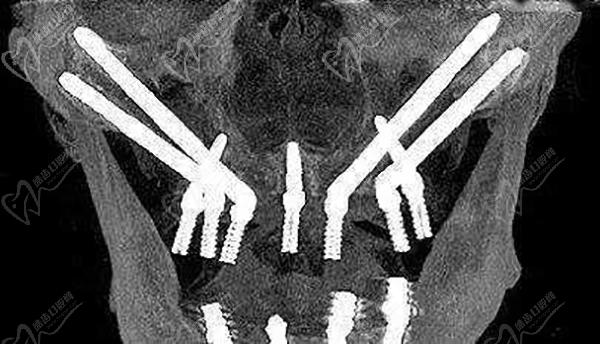

高振華:在九人民醫(yī)院講課,是鼎植醫(yī)生集團(tuán)的疑難種植骨干醫(yī)生,在種植牙領(lǐng)域成就很高,身兼多個國內(nèi)外種植牙協(xié)會重要職務(wù)!高振華醫(yī)生的種植牙技術(shù)特色就是,專攻各類疑難種植病例,對于全口半口無牙頜種植、牙槽骨重度萎縮種植、即刻種植、疑難種植、VIIV穿翼種植、VIIV穿顴種植手術(shù)、TPP穿翼種植、TPP穿顴種植手術(shù)都有著非常深的研究和豐厚的臨床經(jīng)驗(yàn),經(jīng)他操刀的疑難種植病例非常多,遠(yuǎn)超3000例穿顴穿翼種植手術(shù),造福了不少老人,收獲了一口好牙!

黎強(qiáng):鼎植醫(yī)生集團(tuán)創(chuàng)辦人,種植碩士,曾在廣東省口腔醫(yī)院種植中心、上海九人民醫(yī)院口腔種植中心工作30余年,是國內(nèi)做穿顴穿翼種植牙比較早的疑難種植名醫(yī),尤其是對于全口半口無牙頜種植牙有著豐厚的前沿視野和臨床經(jīng)驗(yàn),熟練一日咬合重建技術(shù)、上頜竇內(nèi)外提升等多種植骨技術(shù),能滿足各類牙友的疑難種植需求。

上海鼎植永博口腔門診部穿顴穿翼種植環(huán)境

上海鼎植永博口腔門診部穿顴穿翼種植